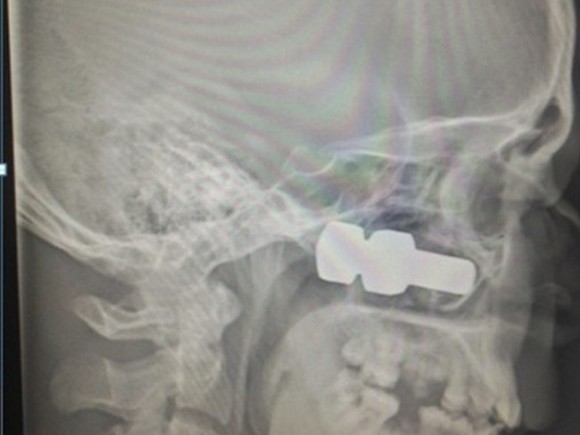

Исследование показало, что лицевые кости Антона в области под глазом пробил болт длиной более 6 см. Попади он чуть выше, и молодой человек остался бы без глаза.

Челюстно-лицевой хирург, кандидат медицинских наук Иван Кан провел Антону сложнейшую операцию — кроме удаления болта нужно было восстановить раздробленные кости лица. Из металлической сетки было сформировано дно глазницы взамен разбитого болтом.